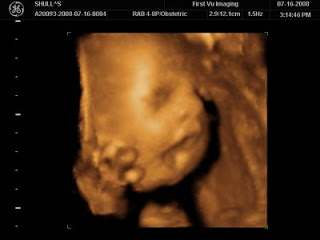

I walked into Andrew’s office and told him it was positive and he looked as confused as I was. After almost two years of trying and six IUIs, how did I randomly get pregnant? I immediately called my doctor and headed to her office and yup…I was preggers. Without trying. I was due September 21.